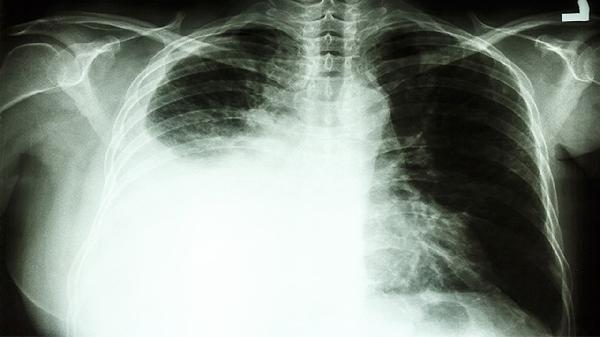

57岁晚期肺癌,化疗到死亡仅七月,肿瘤医生提醒,五种癌症别化疗

57岁确诊晚期肺癌,从开始化疗到离世仅7个月——这样的病例在肿瘤科并不罕见。作为与癌细胞博弈多年的医者,必须坦诚相告:有些癌症真的不适合化疗。